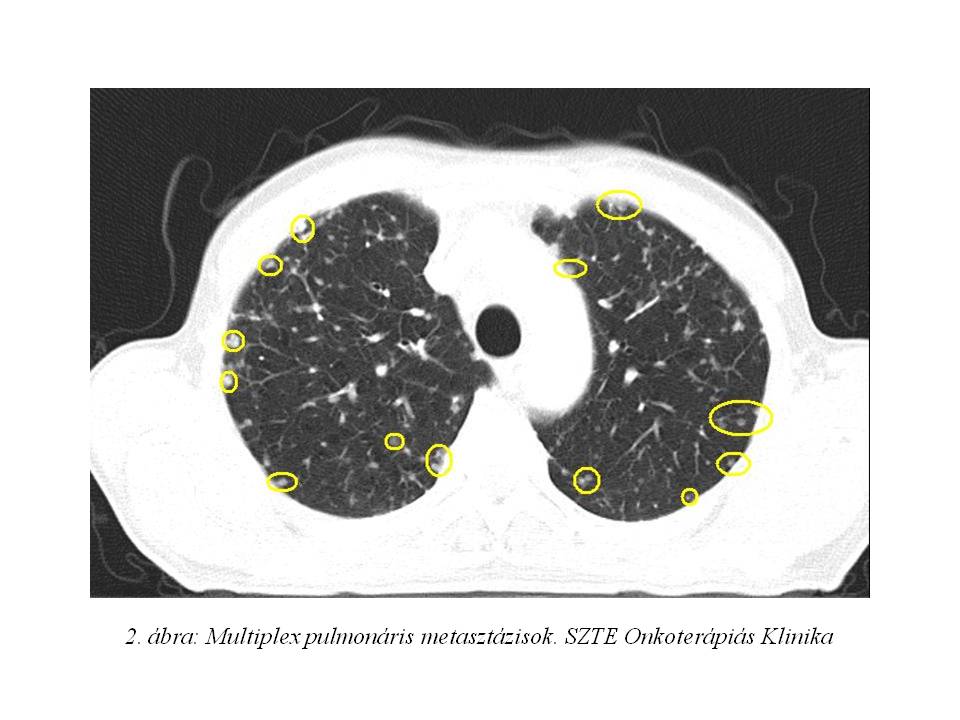

Az akkori staging has-, kismedence CT vizsgálata szerint a primer tumor a bal uretert szűkítette, a májban 4 áttétet írtak le. Mellkas röntgenjén multiplex tüdő áttétek, illetve lymphangitis carcinomatosa lehetősége merült fel. (1. ábra, 2. ábra)

A screening során a beteg staging-jét mellkas CT vizsgálattal egészítettük ki, mely a korábban készült mellkasi röngenvizsgálaton észlelt multiplex tüdőmetasztázisok jelenlétét megerősítette.